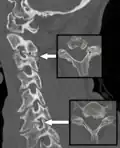

Multiplanar reconstruction and projections

Multiplanar reconstruction (MPR) is the process of converting data from one anatomical plane (usually transverse) to other planes. It can be used for thin slices as well as projections. Multiplanar reconstruction is possible as present CT scanners provide almost isotropic resolution.[104]

MPR is used almost in every scan. The spine is frequently examined with it.[105] An image of the spine in axial plane can only show one vertebral bone at a time and cannot show its relation with other vertebral bones. By reformatting the data in other planes, visualization of the relative position can be achieved in sagittal and coronal plane.[106]

New software allows the reconstruction of data in non-orthogonal (oblique) planes, which help in the visualization of organs which are not in orthogonal planes.[107][108] It is better suited for visualization of the anatomical structure of the bronchi as they do not lie orthogonal to the direction of the scan.[109]